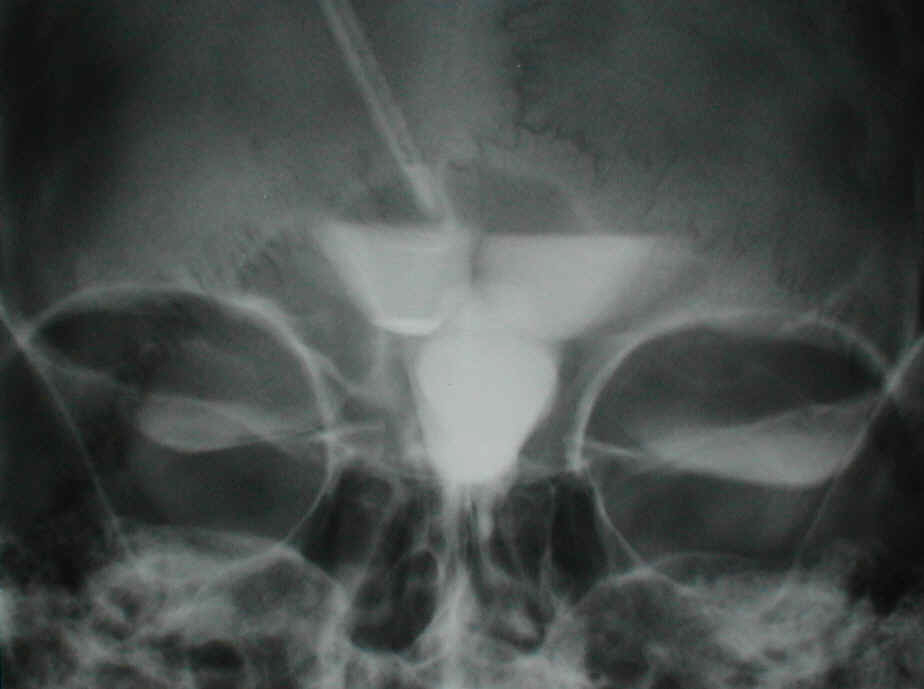

Ventrikulographie

Diese Bilder entstammen unserem Bilderarchiv. Dies deutet schon an, dass dieses Verfahren, - von Ausnahmen abgesehen (z.B. wenn man überprüfen muss, ob alle Ventrikelräume miteinander problemlos Liquor austauschen können, oder ob ein bestimmter Bereich des Ventrikelsystems nicht mit dem übrigen Liquorraum kommuniziert) ein Verfahren aus der Historie der Neurochirurgie darstellt. Hauptsächlich wegen der schönen Bilder zeige ich diese hier. Das obere Bild ist ein Seitenanblick: unschwer ist der von oben kommende Ventrikelkatheter zu erkennen, über ihn wird das Kontrastmittel in den vorderen Teil des Seitenventrikels appliziert und fließt von dort in den daruntergelegenen III.Ventrikel. Von dort aus sollte dann das Kontrastmittel über den Aquädukt in den IV. Ventrikel laufen. Die Aufnahme zeigt jedoch, dass sich nur der vordere (deutlich aufgeweitete) Aquäduktabschnitt füllt, das Kontrastmittel, dann aber nicht weiterfließt. So wurde vor 30 Jahren die Diagnose einer distalen Aquäduktstenose gestellt. Das untere Bild zeigt dasselbe bei einem Blick von vorne. Die halb mit Kontrastmittel gefüllten Seitenventrikel in beiden Hirnhälften und der darunterliegende U-förmige III.-Ventrikel sind gut zu identifizieren.

ABER: wie bereits gesagt (von Ausnahmen abgesehen) hat das Verfahren bei der modernen Methodik der Indikationsstellung bei Verdacht des Vorliegens eines Hydrocephalus nichts mehr verloren.